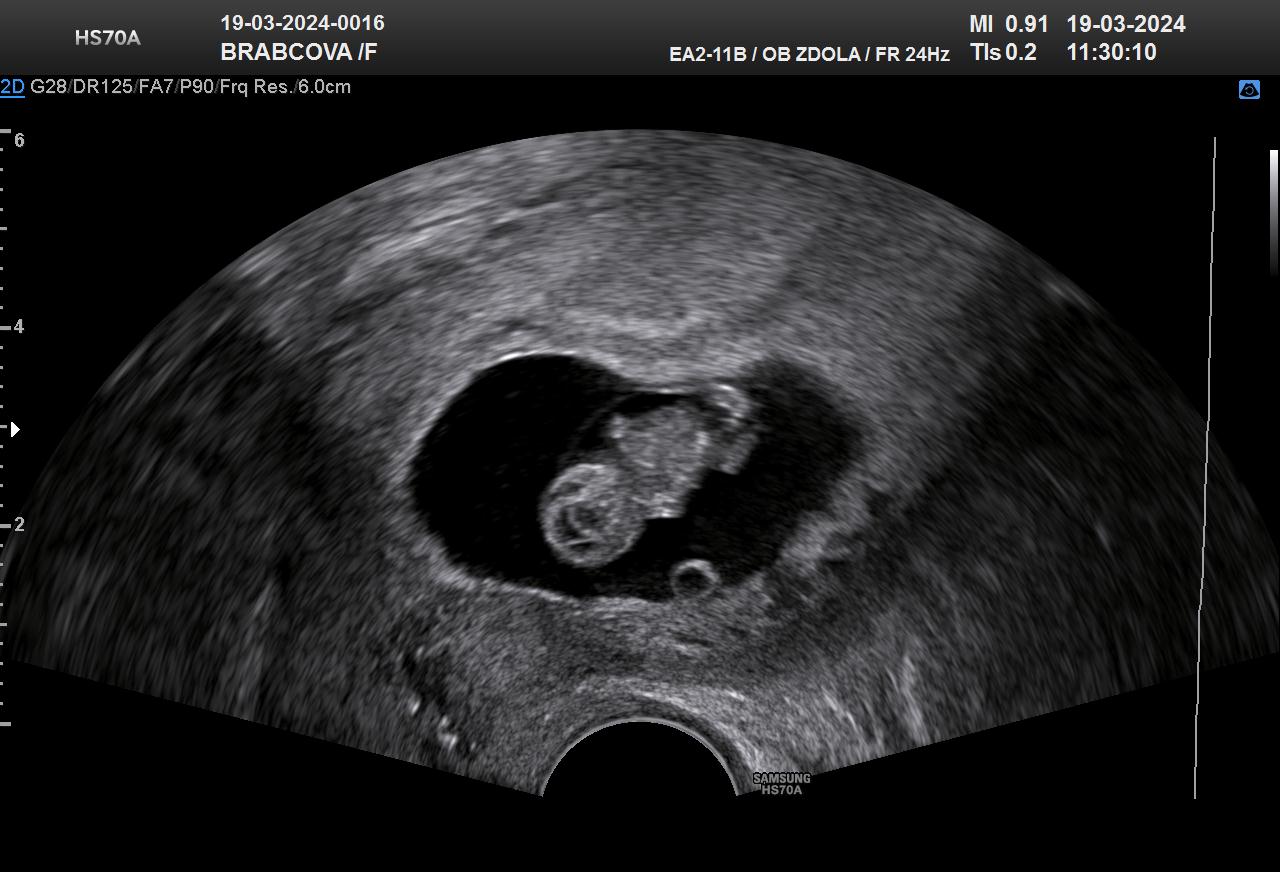

@aquenka tak holky, už mám po kontrole a to maličké pěkně roste dnes 10+1tt, malé odpovídá 10+0tt ❤️ a měří 3,2cm 🥹 na prvni screening jsem objednaná 9.4☺️